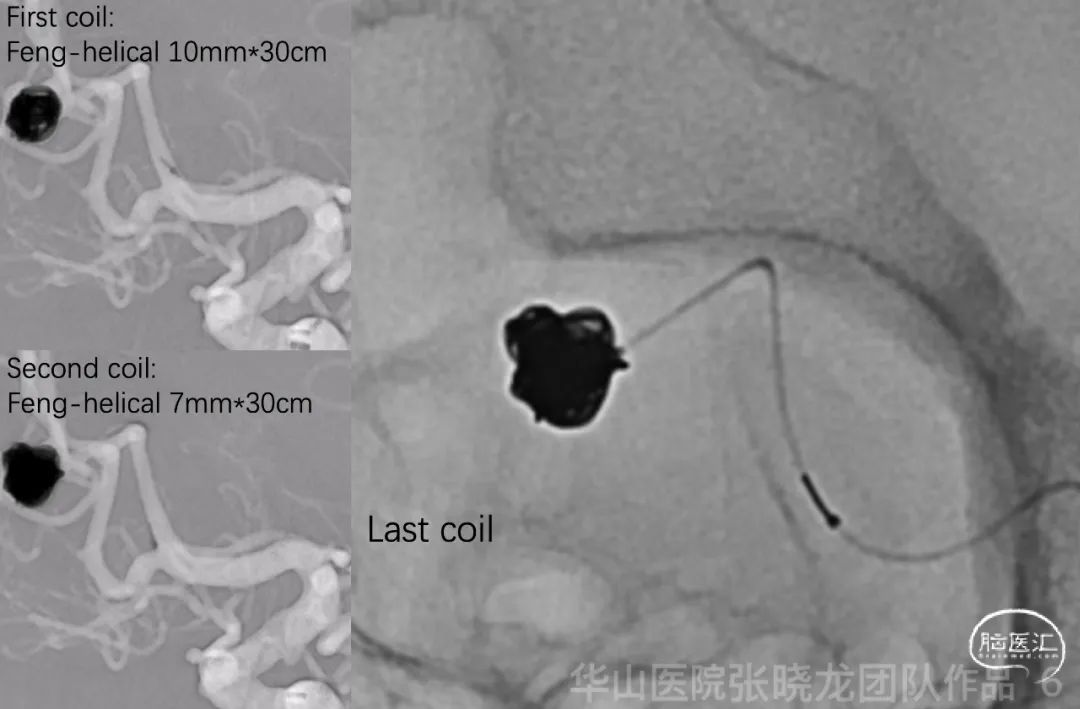

图 6 GIF. 测量动脉瘤大小7.9*7.8mm,瘤颈3.7mm。行全身肝素化。由于髂动脉和腹主动脉迂曲,选用90cm 0.089长鞘置于左侧颈内动脉起始部。115cm 6F通桥中间导管置于颈内动脉颅底处。经导管灌注尼莫地平1ml。直头SL-10微导管在微导丝导引下置于瘤腔。经微导管依次填入4枚弹簧圈(Tonbridge Feng helical 10mm*30cm, 7mm*30cm, 6mm*20cm & Target 360 3mm*4cm) 。